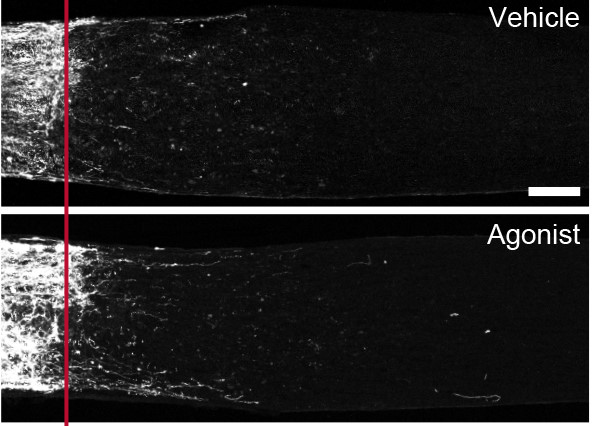

Hall and colleagues instead tested whether compounds that act on GPR88 might protect RGCs from injury-induced cellular damage. They administered these compounds before inducing an injury to the optic nerve and measured the number of RGCs that survived and the density of the optic nerve 2 weeks after injury. The authors could not detect a difference in either metric, suggesting that either GPR88 does not contribute to cell survival, or more than the 5 RGC types identified would require GPR88 expression for a drug to yield a noticeable effect.